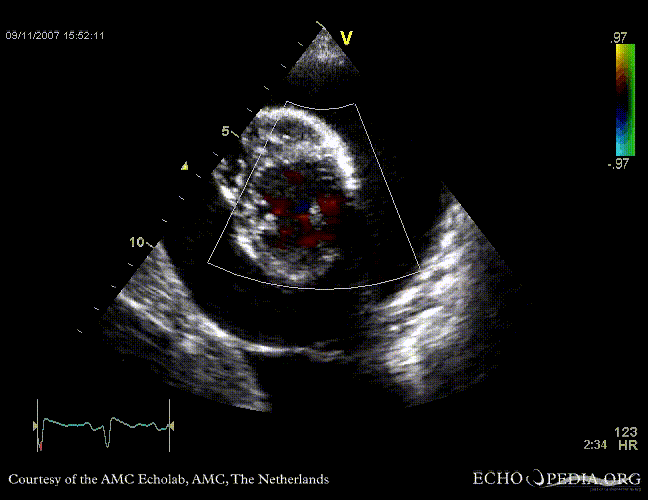

Tamponade

Courtesy of:

J. Vleugels, AMC, The Netherlands

tamponade 2